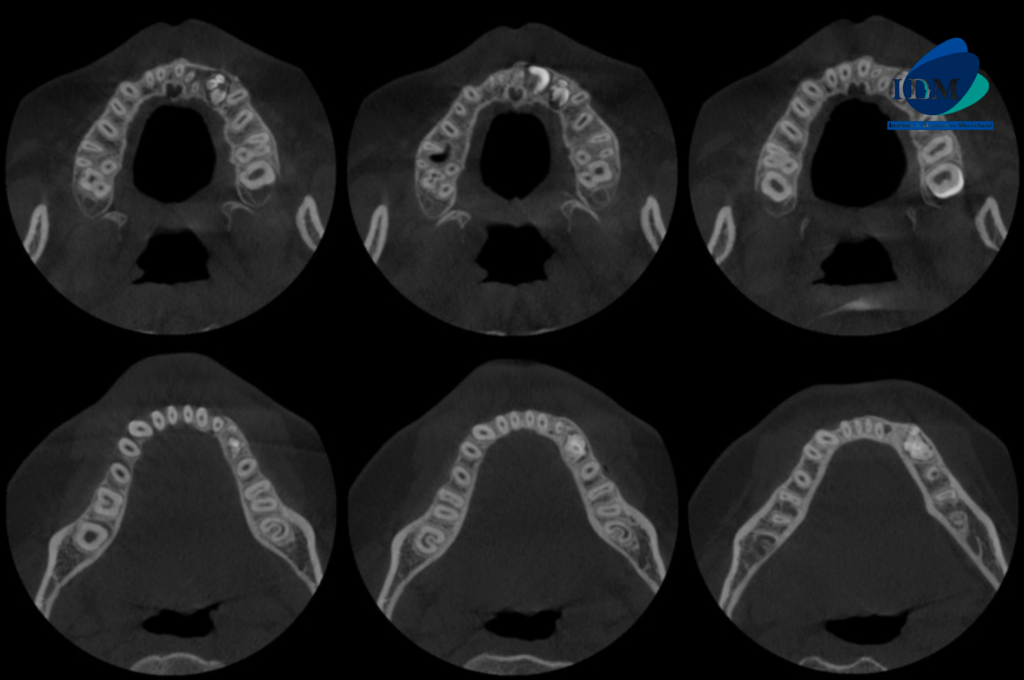

A la evaluación de la tomografía volumétrica (CBCT) en los cortes axiales (Figura 2) y transaxiales (Figura 3), se aprecia imágenes hiperdensas (dentículos) circunscrita con un halo hipodenso, localizada entre los segmentos radiculares de piezas 22 y 24, de limites definidos ocasionando desplazamiento de pieza 23, adelgazamiento de tabla ósea vestibular y palatina compatible con odontoma compuesto. Imagen hiperdensa circunscrita con un halo hipodenso, localizada entre los segmentos radiculares de piezas 73 y 35, de limites definidos, forma irregular, ocasionando el desplazamiento de piezas 34 y 33, adelgazamiento de la tabla ósea vestibular y lingual compatible con odontoma complejo.

CORTES AXIALES